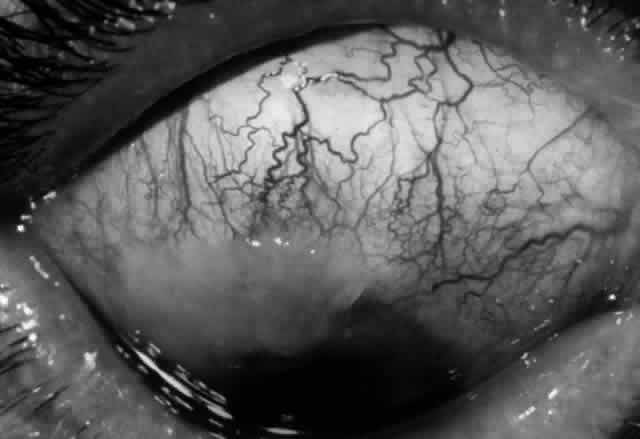

Clinically, the ocular disease in cicatricial pemphigoid (OCP) may present unilaterally in the form of a chronic, recurrent catarrhal conjunctivitis, but it eventually becomes bilateral. Subepithelial fibrosis is characteristic of stage 1 of OCP (Fig. 7). Stage 2 shows fornix foreshortening (Fig. 8), and symblepharon formation is the hallmark of stage 3 (Fig. 9). Stage 4, end-stage disease, is characterized by ankyloblepharon and surface keratinization (Fig. 10). Obstruction of the lacrimal ductules and meibomian gland ducts eventually produces an unstable tear film and progressive sicca syndrome, but it is to be emphasized that OCP is not a dry-eye syndrome until late in the disease course.20 Trichiasis and entropion occur because of the subepithelial fibrosis, with eventual keratopathy, corneal neovascularization, and corneal ulceration and scarring.20

Fig. 10. Stage 4 cicatricial pemphigoid. Progressive shrinkage of the conjunctiva resulted in extreme trichiasis and distichiasis and keratopathy, with compromise of meibomian ductules and lacrimal ductules and the production of a totally dry eye.